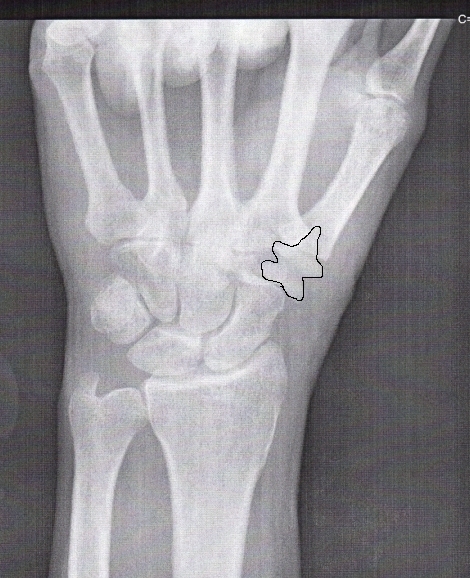

Here's a post-surgery x-ray. The trapezium was removed and replaced with a flexible plastic (maybe nylon or some other appropriate material) appliance. It has a cone shape on the end that was inserted into the end of the first bone of the thumb. |

Here I have (roughly) outlined the appliance. This is exactly the same x-ray as the one above, so you can see the shape of the appliance here and then look for it in the second picture. |